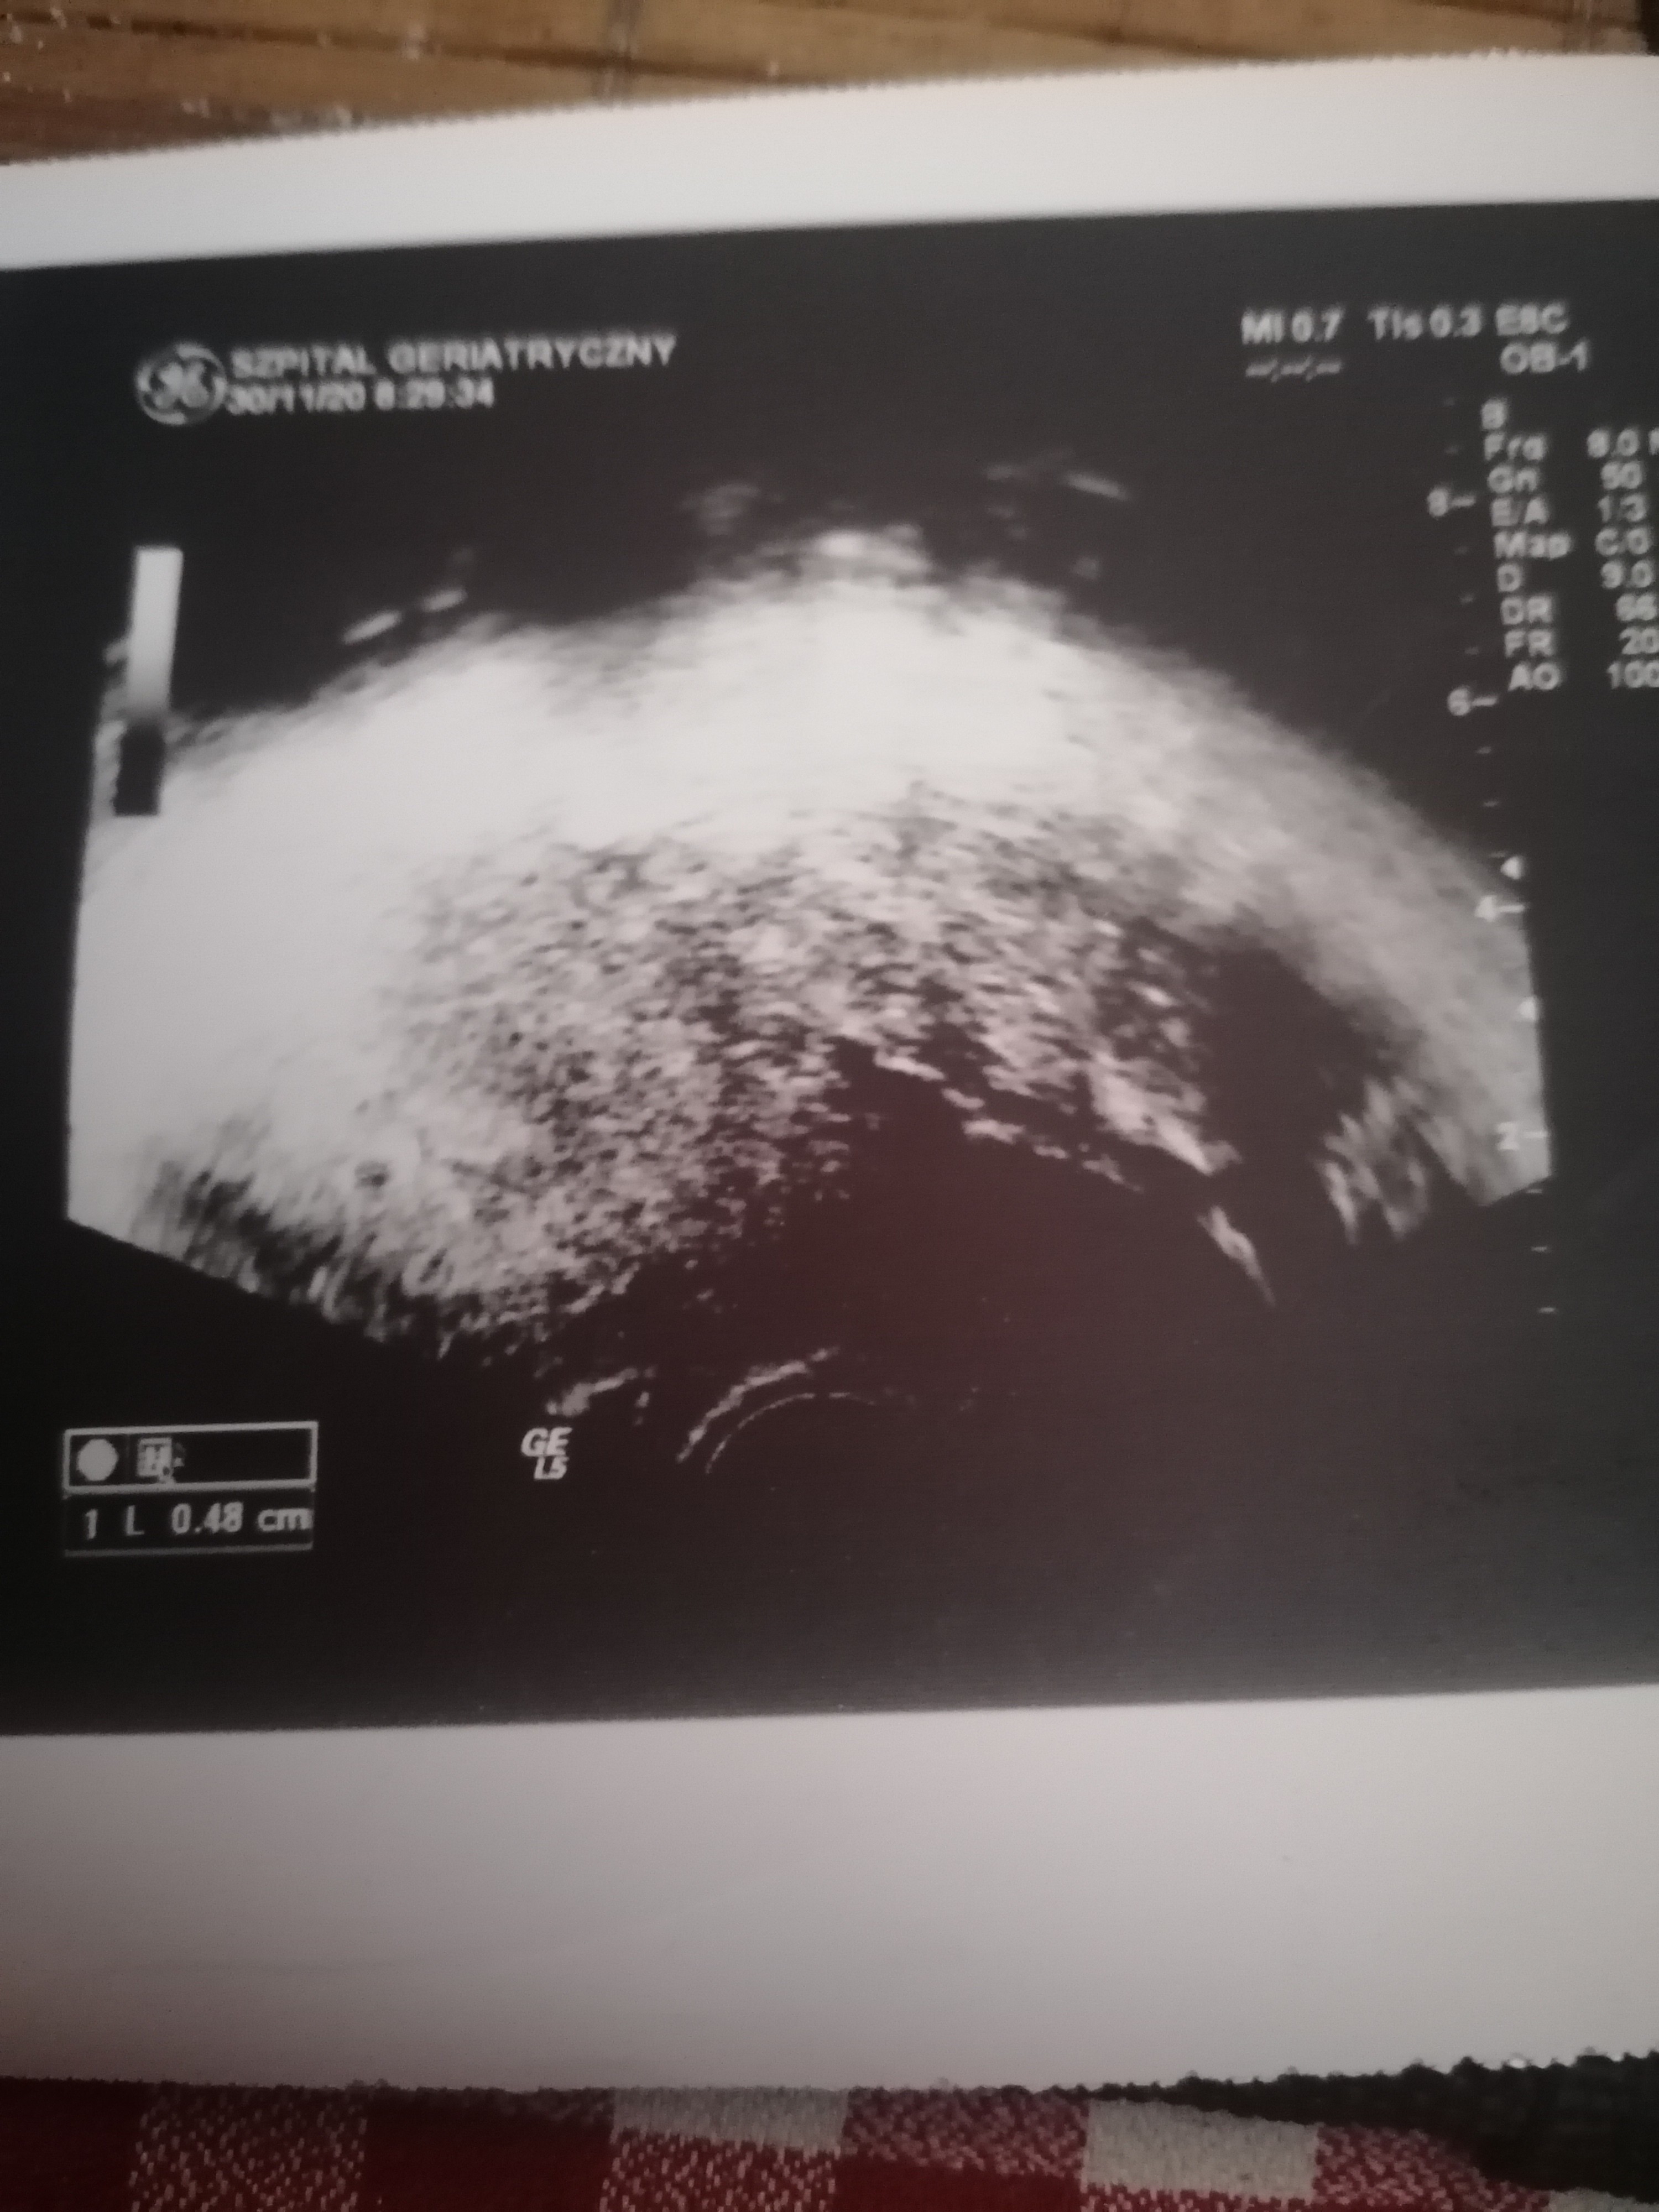

Hmmm, możesz pokazać na zdjęciu gdzie ten pęcherzyk bo ja go nie widzę? Nawet nie widać na zdjęciu żadnych pomiarów. Pęcherzyć oznaczany jest na usg jako GS a u Ciebie brakuje takiego pomiaru. Badałaś betę?

Hmmm🤔 chyba sama sobie tego usg nie zrobiłam 😁 a lekarz wie co widzi i co mówi powiedział że jest pęcherzyk w jamie macicy 5mm to co mam mu nie wierzyć? @ nadal nie ma testy pozytywne wiec ciąża się rozwija a moze se wmawiam 😁☺️ Pozdrawiam